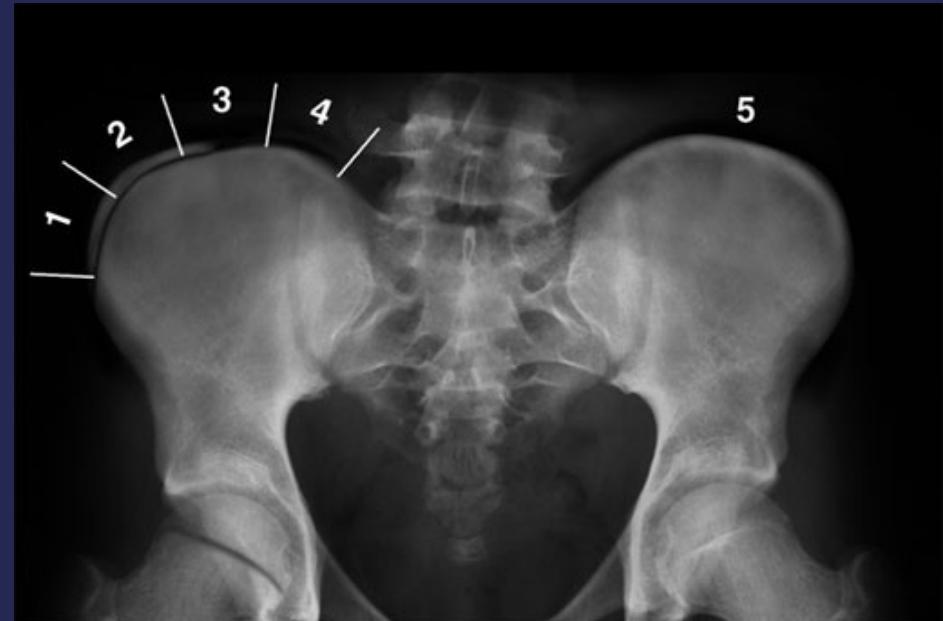

Growth Assessment: Risser Grading

- Measures bony fusion of iliac apophysis

- Range: 0 (no ossification) to 5 (complete bony fusion)

- Lower grade = higher progression potential

Imaging

- X-ray:

- AP and LAT of entire spine (Cobb angle measurement)

- AP pelvis (Risser grade)